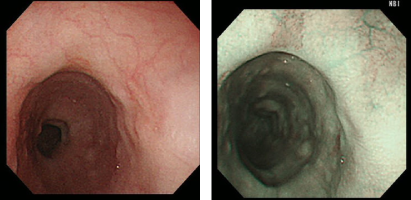

NBI(狭帯域光法)検査

血液中のヘモグロビンに吸収されやすい狭帯域化された2つの波長の光を照らして観察する新しいシステムです。粘膜表面の血管や模様が強調されて表示されることにより通常光では発見しづらい早期食道癌の発見に力を発揮します。

当院では必要に応じてインジゴカルミン染色やヨード染色を用いて精密な内視鏡診断に力を入れています。